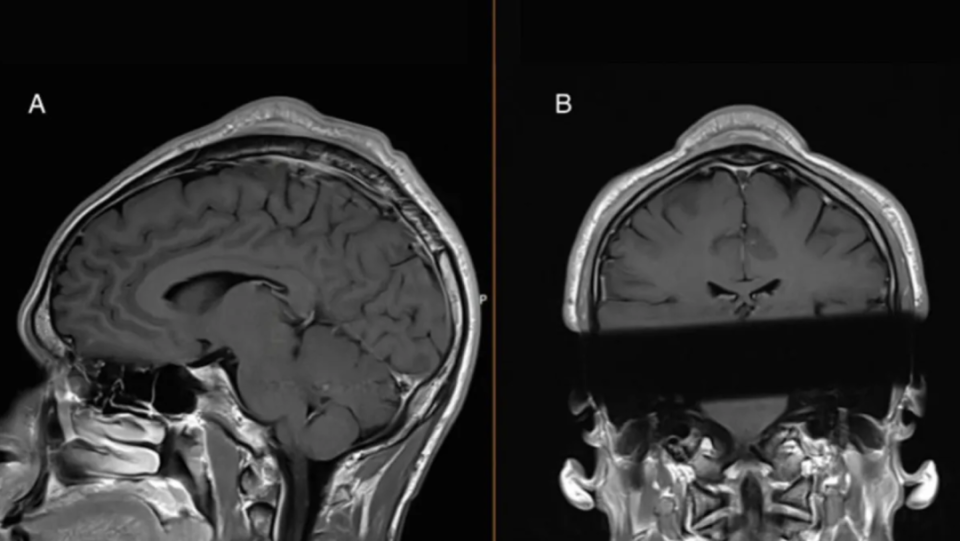

随着霹雳舞(breaking)进入奥运会,越来越多的人们注意到了这一舞种。不过想要学会这一舞蹈,可能要付出不少身体上的代价。最近,医学期刊BMJ Case Reports上发表的一篇病理报告,就提到了霹雳舞者的罕见病症:头转洞(headspin hole)或霹雳舞凸起(breakdance bulge)

患有该病的舞者是一名30岁出头的男性,他练习各种类型的头转(headspin)已有19年多。他每周跳舞五次,每次训练1.5小时;每次训练大约有两到七分钟的时间会对头顶施加压力。

该男子称,五年前,他发现头皮上长了一个肿块,并伴有脱发,也没当回事。但这个肿块不断增大,现在摸起来有些许疼痛感,甚至严重影响到了他的外貌,需要戴帽子才能出门。

医生在他的头顶检测出了一块尺寸约3.3厘米的肿块,还发现肿块上方的皮肤和下方的头骨比周围的组织更厚。不过幸运的是,肿块并没有发生癌变,通过手术很快就被切除了,医生还将他头骨增厚的部分削回到正常厚度。

扫描显示,该男子皮肤下方和颅骨顶部有一个大肿块。|BMJ Case Reports

哥本哈根皇家医院神经外科的专家说:“可能是因为舞者在进行头转时,头骨和头皮等部位与地面反复摩擦,再加上头部需要支撑身体的全部重量,从而引发了炎症,随着时间的推移,微的出血导致皮肤增厚并形成疤痕组织,最终形成了凸起。”